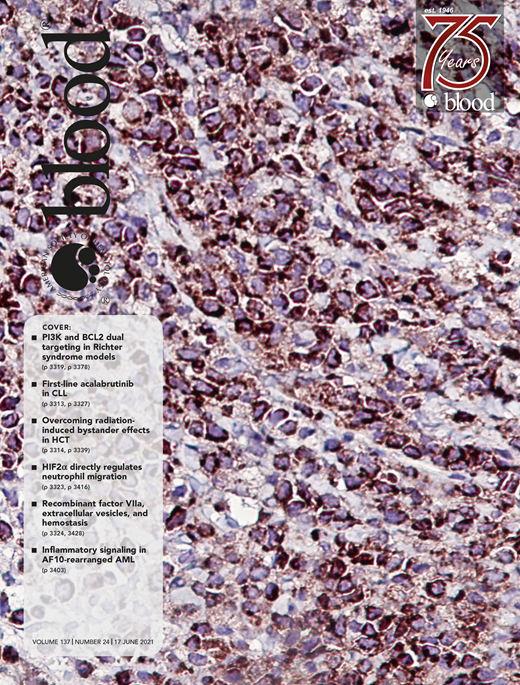

Cover Image

Cleaved caspase-3 immunohistochemistry staining on a tumor mass from a patient-derived xenograft model of Richter syndrome. Treatment with the combination of duvelisib and venetoclax induces apoptosis in Richter syndrome cells. See the article by Iannello et al on page 3378.